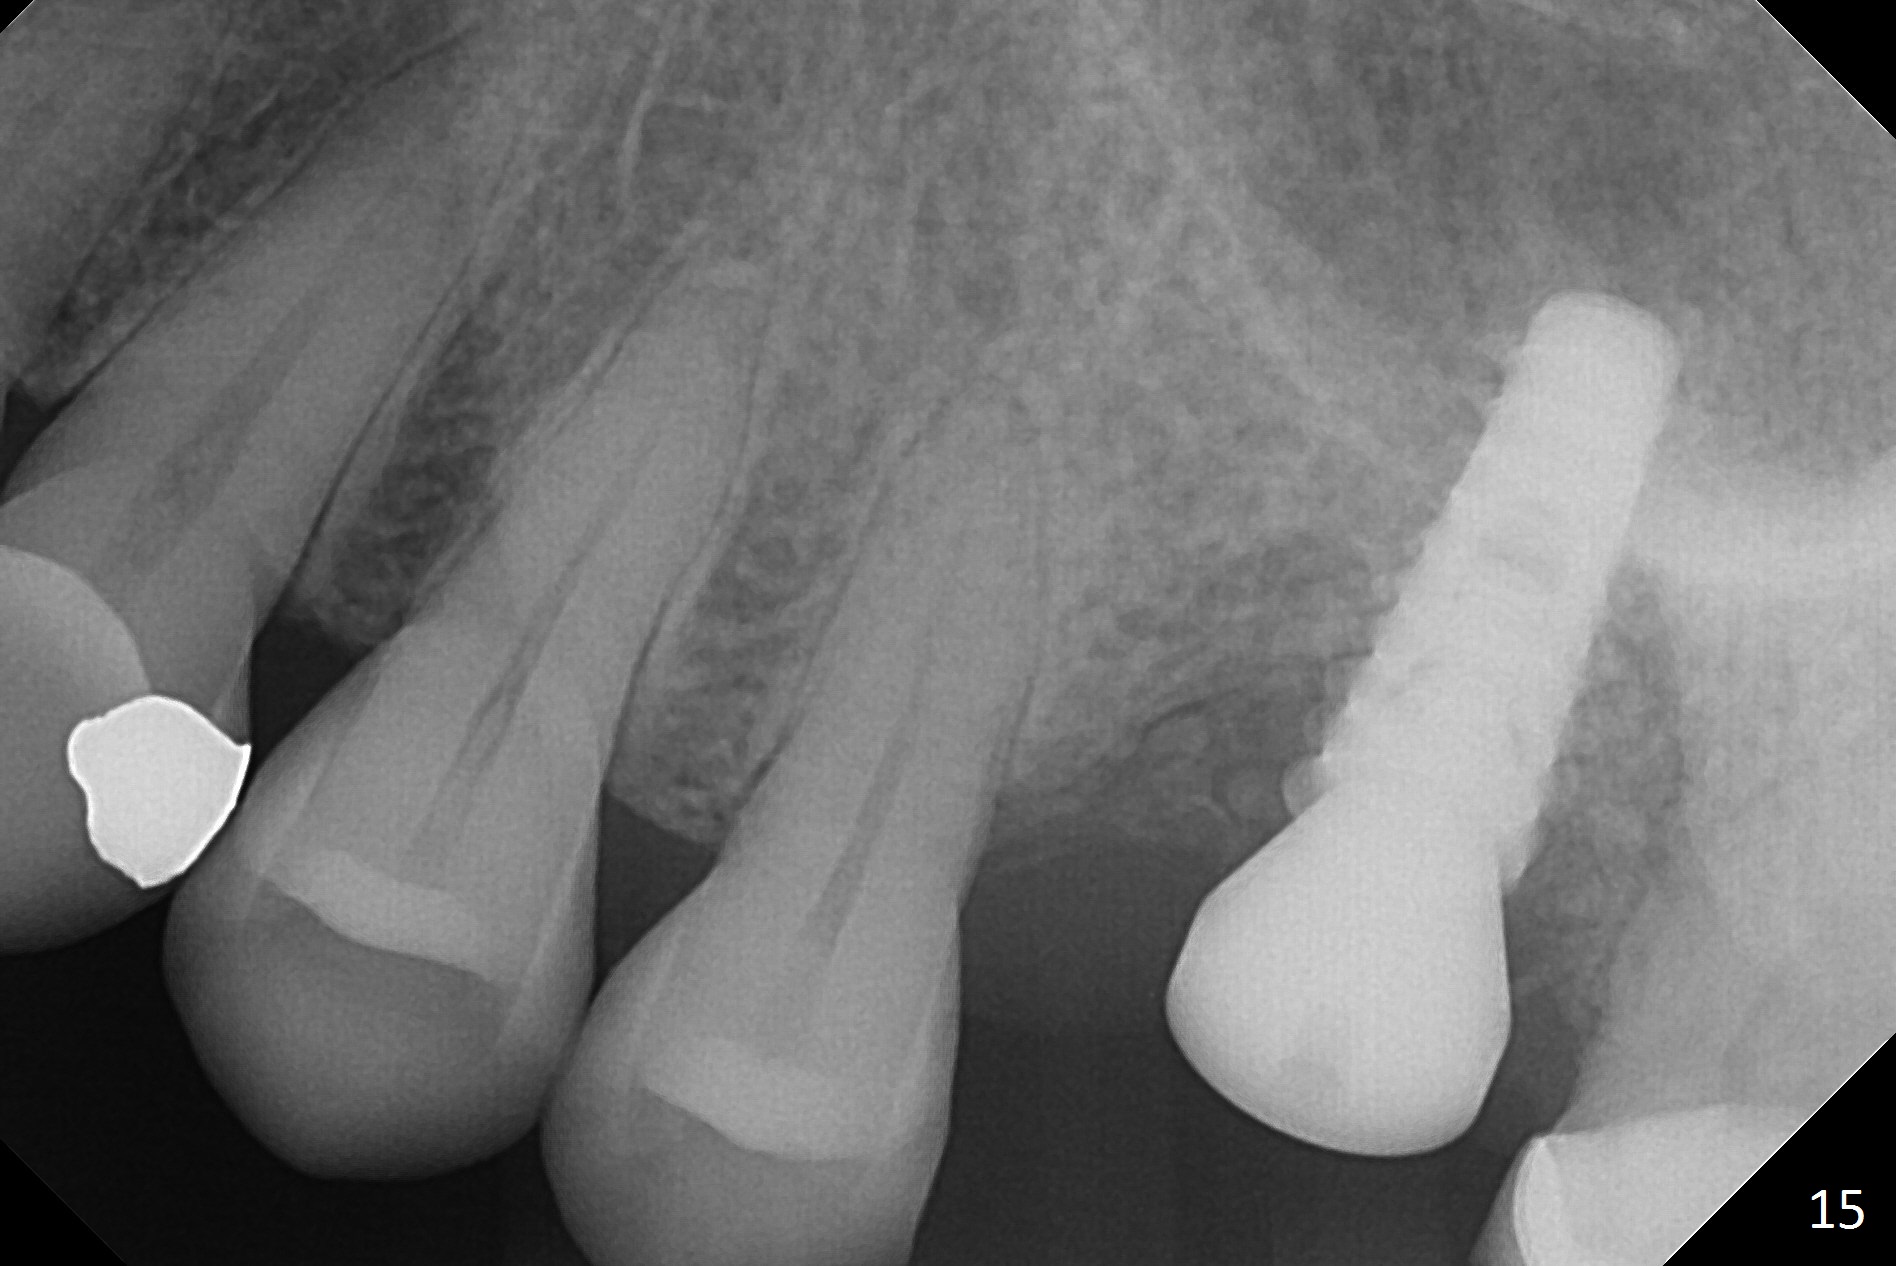

The implant is stable 8 months postop (Fig.15). When a 6x4(3) mm abutment is placed 8.5 months postop, it is distal (Fig.16). The mesiodistal width is 1-2 mm shorter than that at #3, which suggests the mesial shift of the tooth #15. A provisional is fabricated at #14 (Fig.17 P) with supra-occlusion so that there is clearance between the tooth #15 and the opposing one (Fig.18 *). With a separator placed between #14 and 15 (Fig.19), the latter is free to be distalized. Bone volume and density seem to increase 4.5 and 10.5 months post cementation (Fig.20,21, as compared to Fig.15), although the buccal plate remains as concave as shown in Fig.18. One year 5 months post cementation, the patient complains of bad smell from the implant when water pik is being used. It appears that the 1st 2-3 threads are exposed (Fig.22), although the surrounding gingiva remains uninfected. Bone graft is recommended. The site heals without bad smell 7 months post bone graft (2 years 4 months post cementation, Fig.23). The 1st implant thread is found exposed buccal on uncover (regraft?). A small healing abutment is placed because the implant is placed distal (Fig.24). An angled abutment should be tried and #15 crown will be redone. Impression will be taken when the gingiva heals around the provisional crowns.